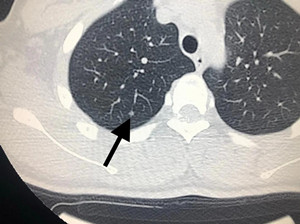

指病灶内实性成分直径大于5mm的mGGN;病灶直径大于10mm的pGGN;具有分叶征、毛糙边缘、毛刺征、空泡征、胸膜凹陷征等恶性征象的GGN;任意大小的pGGN或内部实性成分直径小于5mm的mGGN,若随访过程中出现病灶增大或密度增高;结节出现任何其他浸润性病灶特征。